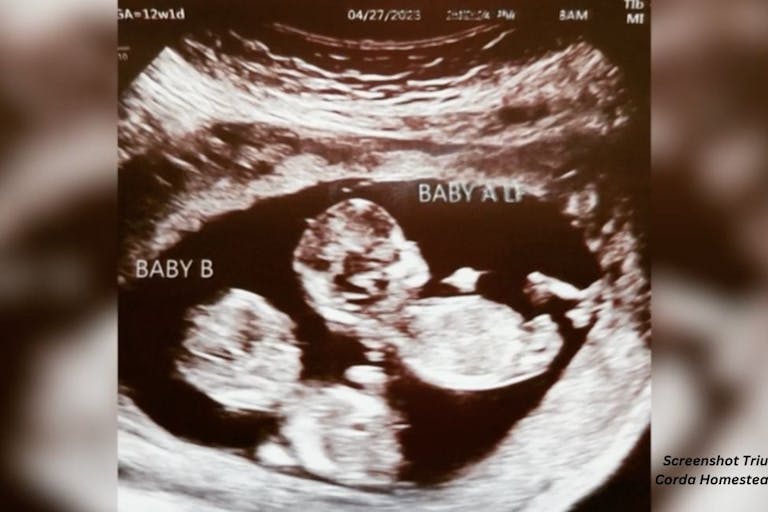

Pregnant mother becomes first to enter trial for medication to help her preborn twins

Anytime the couple has a baby boy, there is a 50/50 chance that he will have the condition, depending on if they get their X chromosome from their father or mother. When they learned they were pregnant with twin boys, Gemma underwent chorionic villus sampling (CVS), which is when a piece of the placenta is taken to test for genetic concerns in a preborn child. It can be carried out earlier in pregnancy (10-12 weeks) than an amniocentesis (15-20 weeks).

As with many genetic conditions, there are ongoing clinical trials to find new ways to treat the conditions and help children have a better quality or quantity of life. Gemma decided to take part in a clinical trial of a medication aimed at helping prevent or slow the symptoms of AHDS. She is the first pregnant woman to go through the trial, which is led by Dr. Roy Weiss, an endrocrinologist at the University of Miami Health System.